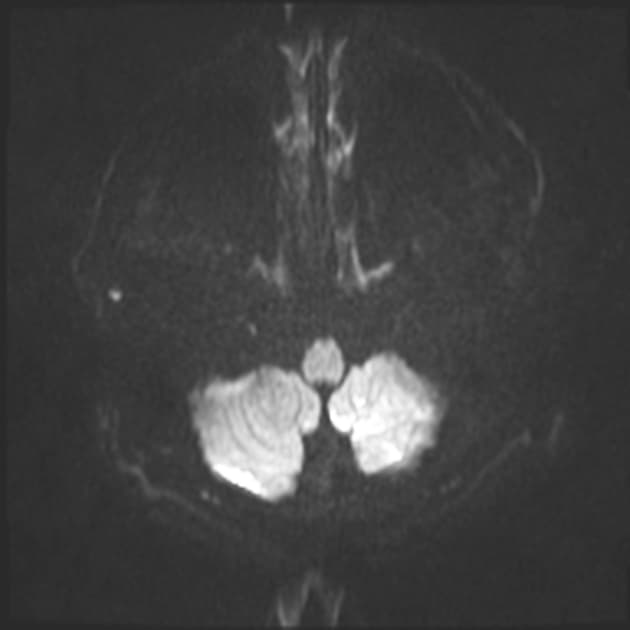

Axial DWI

- Nhiều tổn thương bắt thuốc dạng viền (ring-enhancing) rải rác ở cả hai bán cầu đại não (cerebrum) và tiểu não (cerebellum), các tổn thương này có tín hiệu giảm trên hình ảnh T1 WI, tín hiệu trung gian trên FLAIR WI, tăng quang viền sau tiêm thuốc cản quang, không hạn chế khuếch tán (no diffusion restriction), xung quanh các tổn thương có phù vận mạch (vasogenic edema) bao quanh.

- Nhiều tổn thương bắt thuốc dạng viền (ring-enhancing) rải rác ở cả hai bán cầu đại não (cerebrum) và tiểu não (cerebellum), có tín hiệu trung gian trên FLAIR WI, tăng quang viền sau tiêm thuốc cản quang, không hạn chế khuếch tán (no diffusion restriction), được bao quanh bởi phù vận mạch (vasogenic edema).

- "Việc không có hạn chế khuếch tán giúp phân biệt di căn với áp xe mủ, vì áp xe thường biểu hiện hạn chế khuếch tán rõ rệt."

Trường hợp này cho thấy nhiều tổn thương bắt thuốc dạng viền ở cả hai bán cầu đại não và tiểu não trên bệnh nhân có tiền sử ung thư phổi, rất gợi ý về di căn não. Các tổn thương di căn thường xuất hiện như những nốt tròn rõ ràng, tăng quang viền và kèm theo phù vận mạch lan rộng, mức độ phù thường nặng hơn so với kích thước tổn thương. Việc không có hạn chế khuếch tán giúp loại trừ áp xe não do vi khuẩn, trong khi tính chất đa ổ và phân bố rải rác làm tăng khả năng di căn hơn là u nguyên bào thần kinh đệm nguyên phát – thường là tổn thương đơn độc và nằm ở vùng đại não. Mặc dù u lympho có thể biểu hiện dạng tăng quang viền ở bệnh nhân suy giảm miễn dịch, nhưng thường gặp hơn là tăng quang đồng nhất và hạn chế khuếch tán. Chẩn đoán hình ảnh kết hợp với tiền sử bệnh lý đóng vai trò quan trọng trong việc thu hẹp chẩn đoán phân biệt. Chẩn đoán xác định thường cần sinh thiết, nhưng trong bối cảnh đã biết khối u nguyên phát, đặc điểm hình ảnh thường đủ để chẩn đoán.